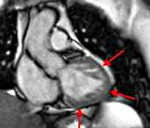

• магнитно-резонансная томография. Использование этого метода в дополнение к Echo-KG позволяет проводить более полную дифференциальную диагностику, чтобы устранить ошибку, особенно в тех случаях, когда верхушку сердца трудно визуализировать. Использование контрастного вещества помогает повысить разрешающую способность исследования и более точно определить внутреннюю структуру левого желудочка, а также диагностировать некомпактный слой на ранних стадиях.